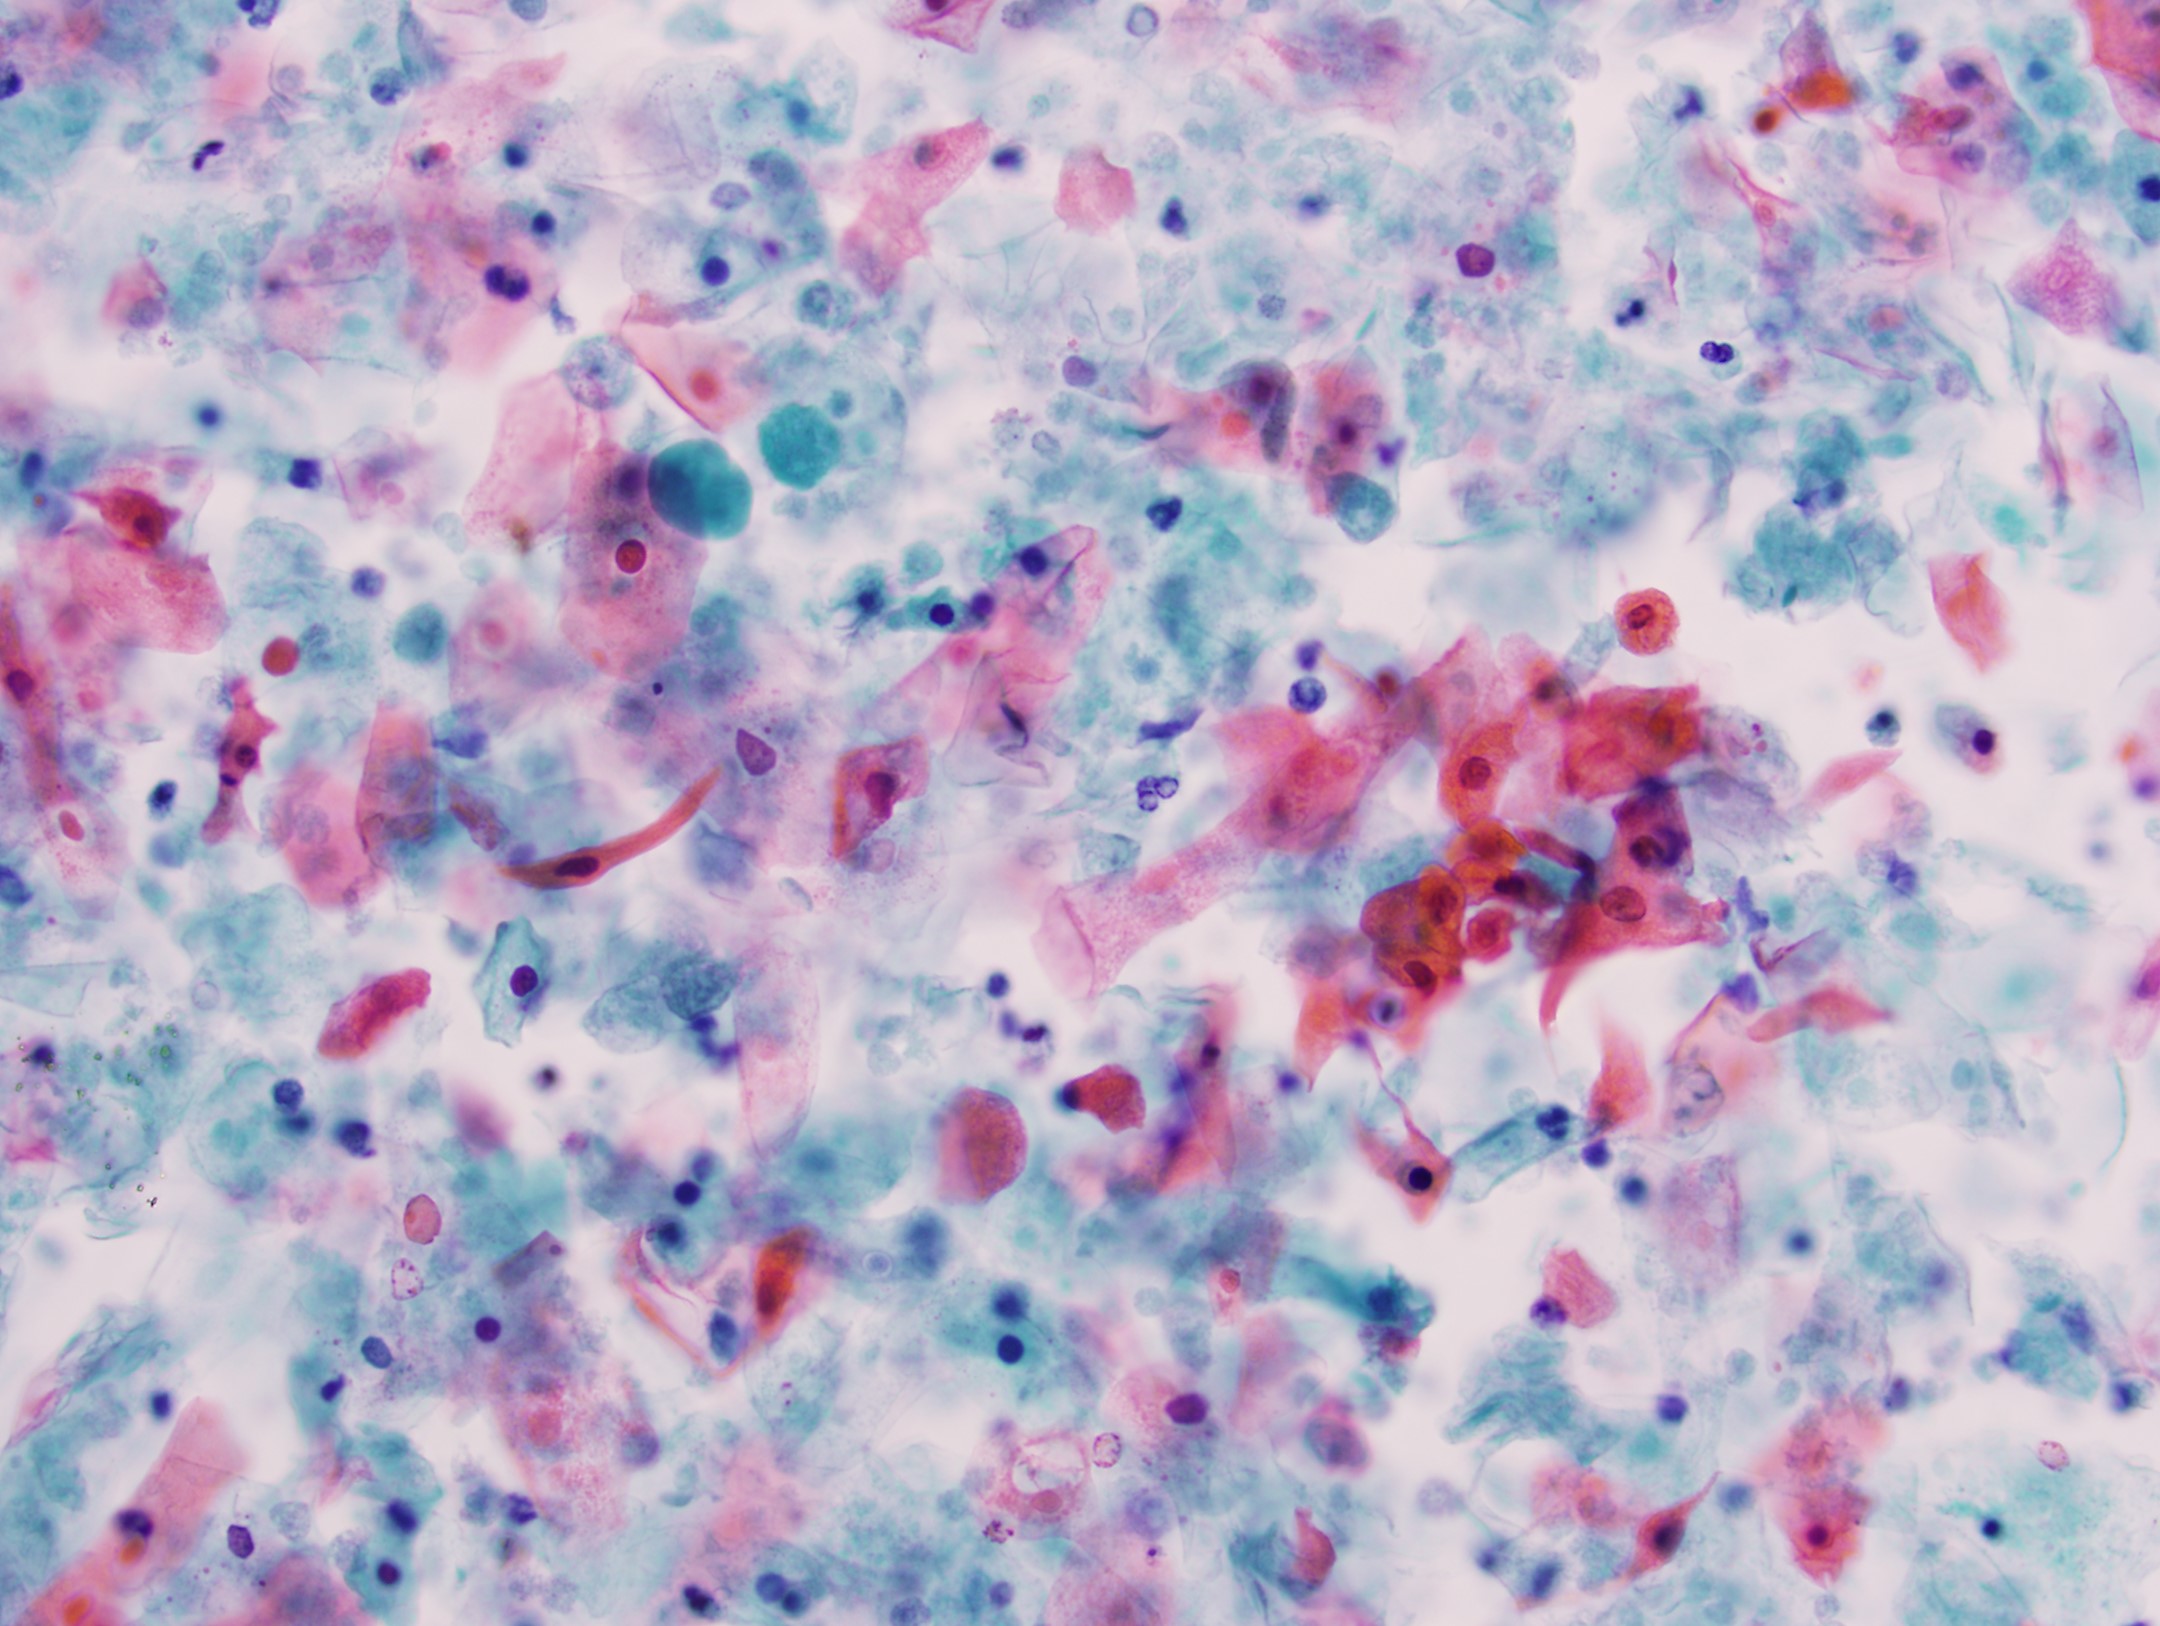

Cytology description

- Mature nucleated squamous cells with variable reactive atypia, anuclear cells and squamous epithelium (Int J Surg Case Rep 2017;41:383, Diagn Cytopathol 2012;40:684)

- Polymorphous lymphocytes and aggregates of epithelioid histiocytes

- Proteinaceous background

- Variable presence of acute inflammation, and bland appearing mucinous ductal cells and ciliated columnar cells

- Scant cellularity, abundant proteinaceous background, lack of squamous cells and epithelial cells, marked atypia of epithelial cells, abundance of lymphocytes pose diagnostic challenges

Cytology images